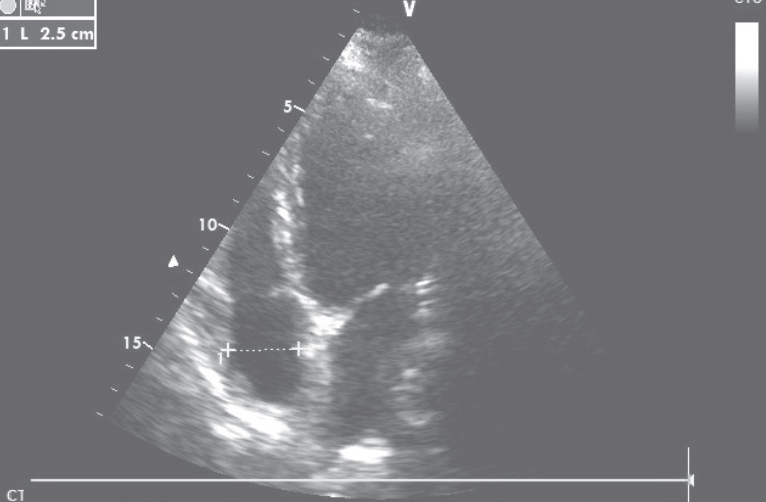

先后予葡萄糖酸钙、乳酸钙(6000 mg/d)、骨化三醇(0.5μg/d)治疗,低钙血症逐渐纠正,1个月后LVEF恢复至30%,NYHA心功能II级。继续补钙治疗,1年后调整每日用药为“乳酸钙3g、α-钙剂2μg、卡维地洛12.5 mg、左甲状腺素150μg”,复查心脏超声,左心室舒张末期内径47 mm,左心室收缩末期内径33mm,LVEF 58%(图5)。

图5 复查心脏超声